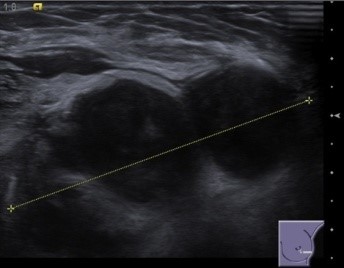

УЗ картина при саркоме молочных желез.